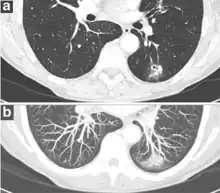

- Growth rate: solid cancers generally doubles in volume over between 100 and 400 days, while subsolid cancers (generally representing adenocarcinomas) generally doubles in volume over 3 to 5 years.[8] One volume doubling equals approximately a 26% increase in diameter.[8]

- Presence of emphysema and/or fibrosis is a risk factor for cancer.[8] In comparison, the typical size doubling are less than 20 days for infections, and more than 400 days for benign nodules.[11]